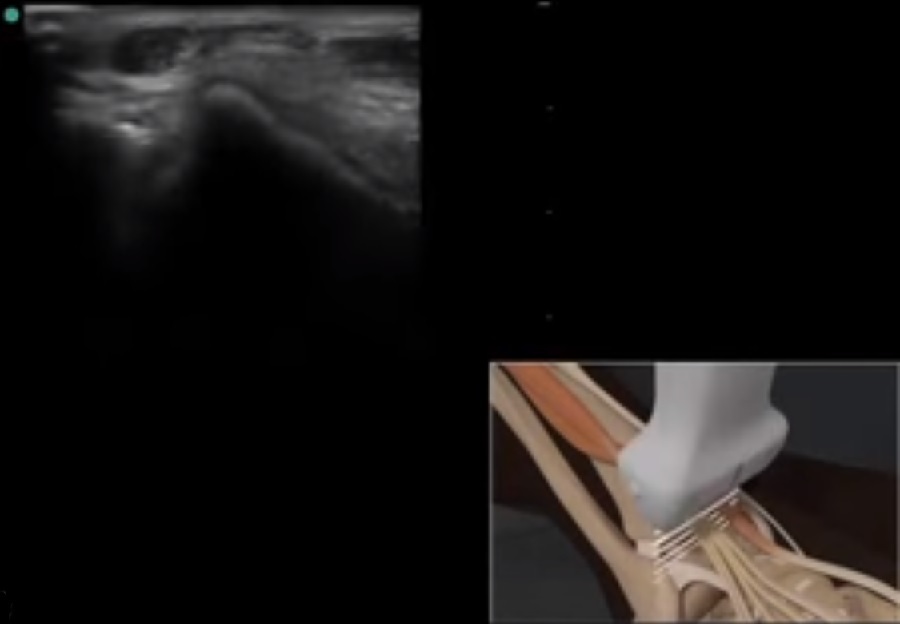

Imagen de la posición del transductor en el extensor largo de los dedos en el pie y el tobillo